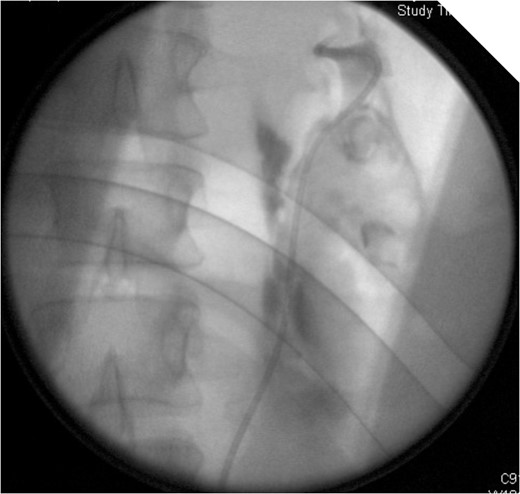

CT IVU- confirmed extravasation of contrast medium around the left kidney and ureter, the rupture being at the level of the PUJ.

Coronal view reconstructions using maximum intensity projection, showing proximal ureteric leak of contrast.